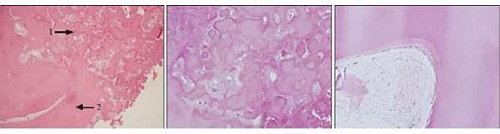

術(shù)后病理檢查。大體見:零碎的灰白軟硬組織一堆,體積約3.0 cm×2.5 cm×0.5 cm,可見多塊似小牙樣結(jié)構(gòu)及碎骨渣。顯微鏡檢查:纖維結(jié)締組織疏密不等,排列成束狀或旋渦狀,其中含有大小不等、排列不規(guī)則的編織骨、板層骨和圓形、卵圓形無細(xì)胞嗜堿性牙骨質(zhì)樣物,骨小梁周圍見成排的成骨細(xì)胞。此外,鏡下還可見多處圓錐形、不規(guī)則牙樣結(jié)構(gòu),釉質(zhì)、牙本質(zhì)和牙髓的組織結(jié)構(gòu)排列如同正常牙(圖3)。術(shù)后病理診斷為:(左下頜骨)骨化纖維瘤伴組合性牙瘤形成,部分區(qū)域細(xì)胞活躍。術(shù)后半年復(fù)查,患者無復(fù)發(fā)。

(2)病理學(xué)檢查。OF鏡下為增生的纖維組織和一些大小不等、排列不規(guī)則的骨小梁和鈣化團(tuán)塊,骨小梁從未成熟幼稚骨小梁到成熟板層骨小梁均可見到,其周邊可見成排的成骨細(xì)胞。FD由細(xì)胞豐富的纖維組織構(gòu)成,內(nèi)含編織骨形成的孤立的骨小梁,這些幼稚的骨小梁彼此缺乏鏈接,無板層結(jié)構(gòu),常呈英文字母形,其邊緣通常沒有成骨細(xì)胞圍繞。張佩瑜等認(rèn)為,光學(xué)鏡下HE染色、網(wǎng)狀纖維染色及偏光顯微鏡觀察相結(jié)合有助于OF和FD的鑒別診斷,因為OF組織中有發(fā)育成熟的板層骨,而FD病變中骨小梁屬于編織骨,偏光顯微鏡下,板層骨有明暗平行的雙折光帶,編織骨的雙折光帶雜亂。本例除有典型OF的鏡下改變之外,還呈現(xiàn)出經(jīng)典的組合性牙瘤的特征(圖3)。